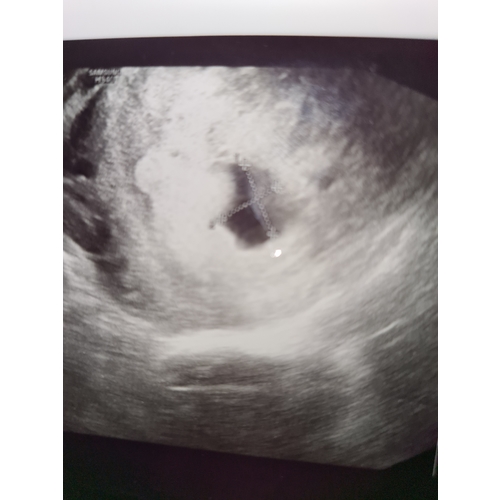

Hm lijkt me wat groot om 10wkn miskraam te zijn dat niet groeide, denk eerder combo van vruchtzak, moederkoek en oudbloed

Ik denk het ook. Vruchtzak waarschijnlijk.

Iets later, met het verversen van het water, zag je steeds duidelijker wat het was. Inderdaad een vruchtzak met een onvolgroeid vruchtje in ons geval.

Wat verdrietig voor jullie! Als drie specialisten zagen dat het niet groeide dan had het hoe dan ook geen kans in de wereld gehad. Goed idee om het in water te stoppen zodat duidelijk wordt wat het is. Het ziet eruit als stolsels, maar het geeft wellicht rust als je het beter kunt zien. Sterkte en hopelijk gauw weer zwanger van een gezond kindje! ❤️

Dit is waarschijnlijk het deel van de placenta die in je aan het groeien was. Als je het in een bak koud water legt kun je het waarschijnlijk goed zien. En misschien kun je dan een kleiner vruchtje ook ontdekken. Het heeft mij in september wel geholpen om goed afscheid te nemen.